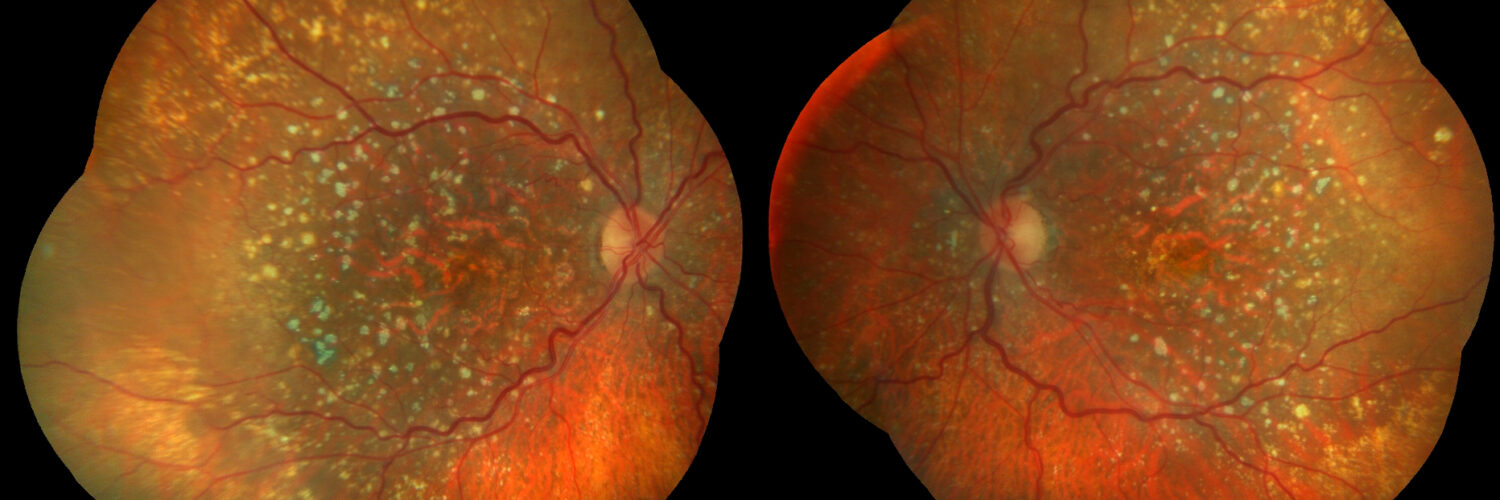

Pocas condiciones suponen un reto tan complejo como la Degeneración Macular Asociada a la Edad. El Sistema de Visión Biónica PRIMA se presenta como el primer salto cuantitativo probado hasta la restauración de parte de la visión funcional.

El paciente con DMAE que llega a una consulta de baja visión no es un paciente ciego: es un paciente con pérdida central bilateral y visión periférica funcionalmente preservada. Comprender este perfil antes de abrir la historia clínica condiciona toda la estrategia rehabilitadora. Esta miniguía abarca desde la evaluación funcional hasta la rehabilitación y coordinación multidisciplinar.